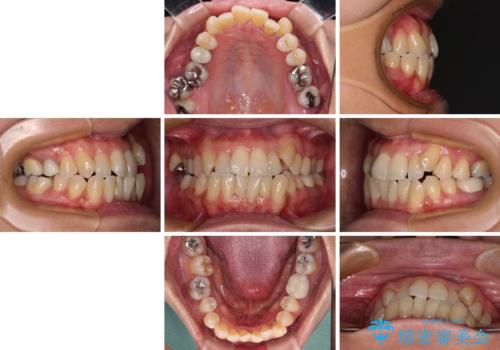

受け口と八重歯を改善 インビザライン矯正治療

- 前歯のデコボコや八重歯を治したいとのことで来院された患者様です。

受け口傾向の骨格であり、前歯はクロスバイトまたは切端咬合となっており、下顎を中心に歯列全体の後方移動を行い、IPR(歯と歯の間を削る)によってデコボコが解消するように設計し、インビザラインにより治療を行うこととしました。